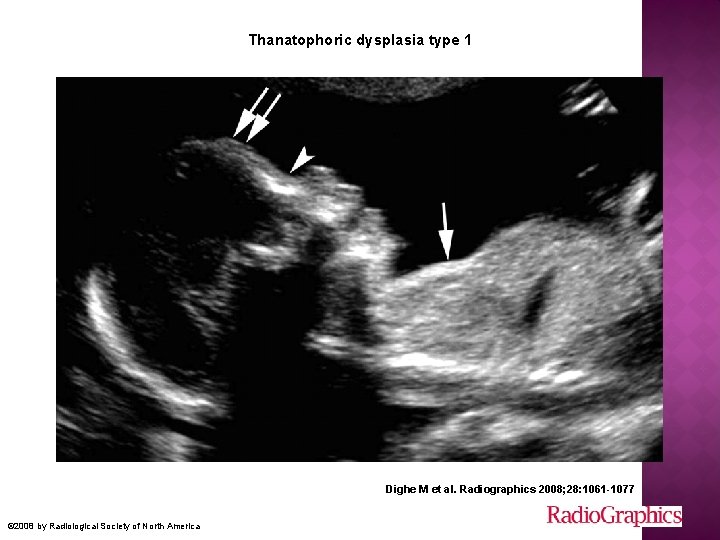

� Tanatrofik « ölümcül » � En sık letal fetal iskelet displazisi � Fibroblast growth factor receptor 3 (FGFR 3) gen mutasyonu � OD (genellikle) � 2 tipi var Genellikle erken yenidoğan döneminde pulmoner hipoplazi nedeniyle kaybedilir

Ciddi ekstremite kısalığı Tip 1’ de eğimli Tip 2’ de düz � Tip 1 makrosefali frontal bossing burun kökü basık � Tip 2 cloverleaf trident hand torakal hipoplazi telephone receiver Ekstremitelerde ileri derecede açılanma ve kısalık Uzun kemikler düz ve kısa

Thanatophoric dysplasia type 1 Dighe M et al. Radiographics 2008; 28: 1061 -1077 © 2008 by Radiological Society of North America